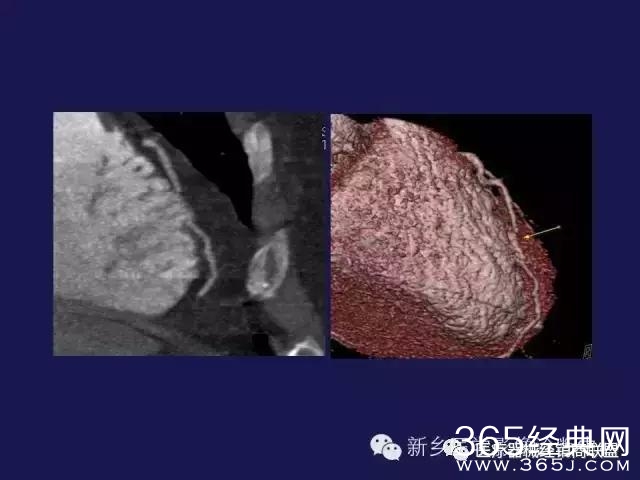

CT、MRI很难?NO,今日我们一起来学习一下如何读CT、MRI!

内行看门道:

整整90张图

强烈建议大家收藏后再观看